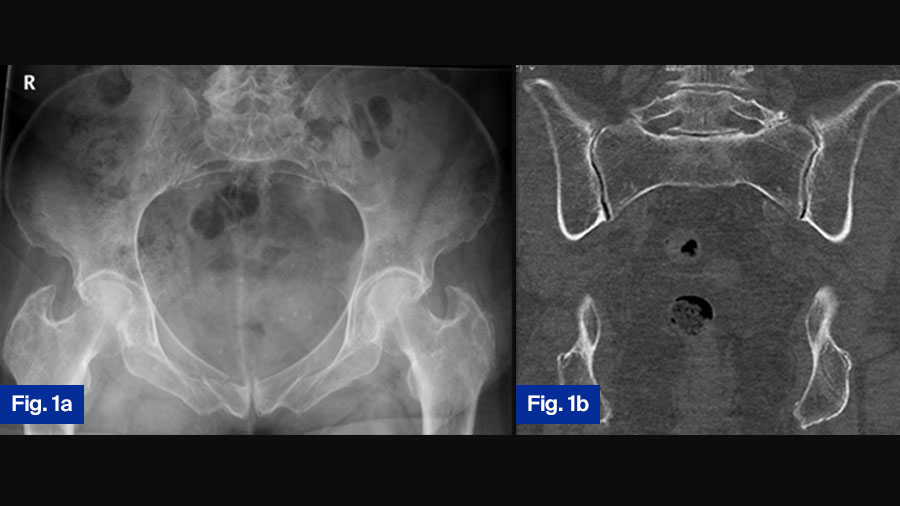

Case study 1: 78-year-old female with progressive fragility fracture

Fig. 1. A seventy-eight-year-old female suffered a domestic fall. The pelvic inlet (a) revealed a slightly displaced fracture of the right pubic ramus. A pelvic CT was taken to exclude fractures of the posterior pelvic ring. On the coronal reconstruction of the posterior pelvis (b), no fracture can be detected. The fracture was classified as FFP Type Ia and conservative treatment initiated.

Due to persisting pain, a second CT was taken one month later. On the coronal reconstruction of the posterior pelvis, a non-displaced fracture of the lateral mass of the sacrum on the left side was now visible (c). Conservative treatment was continued. Because of persistent pain with restricted mobility, a third pelvic CT was taken one month after the second.

The coronal reconstruction of the posterior pelvis revealed an additional fracture of the lateral mass of the sacrum on the right side (d). The fracture progressed from FFP Type Ia to FFP Type IIc.